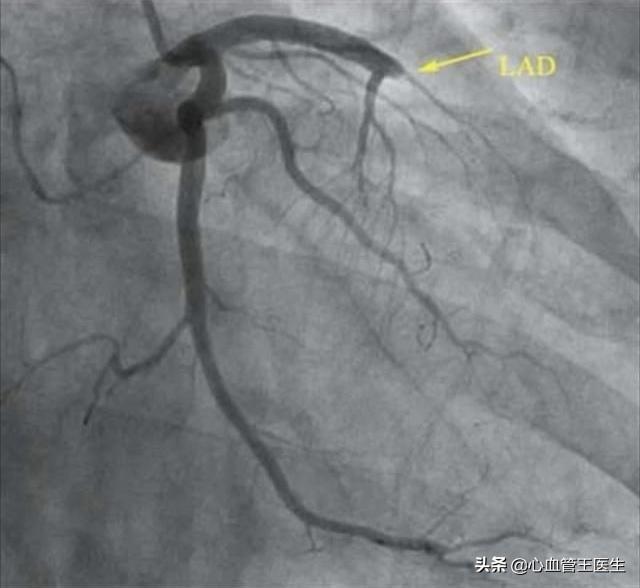

Comment se produit la sténose cardiovasculaire ?Le changement pathologique sous-jacent à la sténose cardiovasculaire est l'athérosclérose, d'où le nom complet de la maladie coronarienne : maladie coronarienne athéroscléreuse. De toute évidence, la sténose cardiovasculaire est causée par la formation de plaques d'athérome, dont la taille augmente progressivement, entraînant un rétrécissement graduel des vaisseaux sanguins jusqu'à ce qu'ils soient complètement obstrués. La rupture soudaine de la plaque, entraînant la formation de caillots sanguins, est un facteur de développement de l'infarctus du myocarde.

Toutefois, s'il est impossible d'inverser la formation de la plaque, il est possible de la ralentir grâce à des médicaments et à des interventions sur le mode de vie. C'est pourquoi de nombreuses personnes âgées peuvent vivre aussi longtemps et en bonne santé que les personnes normales, même si elles présentent une plaque. D'une manière générale, les médecins évaluent le risque élevé de maladie cardiovasculaire, ainsi que la sténose de l'artère coronaire de plus de 50 % des patients diagnostiqués avec une maladie coronarienne, il est nécessaire de commencer un traitement médicamenteux. Les médicaments couramment utilisés comprennent les statines stabilisatrices de plaque telles que le Ruijie, les médicaments antiagrégants plaquettaires tels que l'aspirine, etc. qui est le médicament de base, mais aussi les médicaments antihypertenseurs pour la maladie d'origine, les médicaments hypoglycémiques, etc. Les esters, tels que le mononitrate d'isosorbide Xincang, etc., sont également des médicaments de base. Pour les patients souffrant d'une sténose cardiovasculaire à 80 %, l'état a été prédit comme étant plus grave, et l'on pense généralement que lorsque la sténose est supérieure à 70 %, le patient devra subir la pose d'un stent pour débloquer les vaisseaux sanguins obstrués et aider à rétablir l'apport sanguin normal au myocarde, faute de quoi le patient peut être confronté à un infarctus à tout moment !的Risques. En d'autres termes, pour les patients présentant une sténose cardiovasculaire de 80 %, il peut être difficile de maintenir la vie du patient avec la médecine traditionnelle chinoise ou la médecine occidentale, sans parler d'une guérison complète, et seule la pose d'un stent ou d'un pontage peut sauver la vie du patient.

Une sténose cardiovasculaire de plus de 50 % est appelée maladie coronarienne, lorsqu'elle est supérieure à 70 %, une angine peut survenir, et lorsqu'elle est de 80 %, il s'agit déjà d'une sténose sévère. Qu'elle soit stable ou instable, l'angine peut survenir après un effort, une activité ou un exercice. Si elle est instable, l'angine peut survenir même au repos, et même une rupture de plaque peut se produire, formant un caillot sanguin et déclenchant un infarctus du myocarde.

Pour 80 % des sténoses, il est nécessaire de mener une vie saine, d'arrêter de fumer et de boire, de contrôler son poids, d'avoir une alimentation saine et de suivre un traitement médicamenteux régulier ; même une partie de la population a besoin d'une endoprothèse ou même d'un pontage pour résoudre cette sténose grave.

3. la disparition des symptômes ne signifie pas la guérison, mais seulement le contrôle ; sans oublier comment la sténose de 80 % a-t-elle été diagnostiquée ? S'agit-il d'un scanner coronaire ou d'une angiographie coronaire, s'agit-il d'un vaisseau majeur ou d'un petit vaisseau ? Le scanner ou l'angiographie ont-ils été revus après la guérison, et de combien la sténose de 80 % a-t-elle diminué après l'examen ?